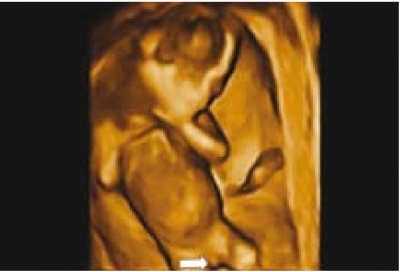

Sagittal sign שתואר לראשונה על ידי Emerson וחבריו[4] הוא הסמן הסונוגרפי המקובל ביותר לקביעת מין העובר בשלבי ההיריון המוקדמים. העובר נסרק בחתכים סגיטליים בקו האמצע. באזור העכוז הנסרק בחתך זה, ניתן לזהות בליטה שמייצגת את הדגדגן או את איבר המין הזכרי. כאשר כיוון הבליטה כלפי מעלה, מין העובר זכר (תמונה 1) וכיוון כלפי מטה מבטא מין נקבה (תמונה 2). שימוש בסמן סונוגרפי זה אפשר לזהות מין העובר ב-71 אחוז (5\7) מהעוברים בשבוע 10 עד 11.9, אך האבחנה הייתה נכונה ב-60 אחוז (3\5) בלבד. דיוק האבחנה עלה עם התקדמות גיל ההיריון ל-75 אחוז, 100 אחוז, 98 אחוז ו-100 אחוז בשבועות 13.9-12, 15.9-14, 16-17.0 ו-18-20.4, בהתאמה[4]. דיווחים רבים אחרים דיווחו על אבחון מין העובר בסוף הטרימסטר הראשון ותחילת השני (14-4) (ראו טבלה 1).

ברונשטיין וחבריו[7] דיווחו שדיוק אבחון מין העובר על ידי אולטרסאונד נרתיקי עולה עם הניסיון, כך שבשנתיים הראשונות לשימוש באולטרסאונד נרתיקי, המין אובחן בדיוק של 76 אחוז ועלה ל-80 אחוז בשנתיים לאחר מכן בין השבועות 13–14 להיריון, ובשבוע 15-16 הדיוק עלה מ-88 אחוז בשנתיים הראשונות לניסיונם ל-96.7 אחוז בשנתיים לאחר מכן. בעבודה זו, מין זכר נקבע על סמך הדגמת מבנה דמוי כיפה (Dome sign) המייצג שק אשכים (תמונה 3) בעוד מין נקבה נקבע על סמך הדגמת שניים או ארבעה קווים מקבילים (Parallel lines) המייצגים את השפתיים הקטנות והגדולות (תמונה 4) . סימנים סונוגרפיים נוספים בעבודה זו[7] היו הדגמת קו אקוגיני הנמשך מבסיס ועד קצה איבר המין הזכרי ומייצג קו האמצע של הפניס (תמונה 5) וכיוון הפאלוס העוברי (כלפי מעלה מייצג זכר וכלפי מטה נקבה).

אולטרסאונד תלת ממדי - מנסיוננו, שימוש באולטרסאונד תלת ממדי אינו מוסיף משמעותית לאבחון מין העובר, במיוחד בטרימסטר הראשון ותחילת הטרימסטר השני ולעיתים יכול אפילו להטעות (תמונה 6). Benoi[9] ואחרים[31][32] הגיעו למסקנה שאכן התלת מימד אינו עוזר לאבחון מין העובר אך השימוש בחתכים (Sectional planes) לעיתים יכול לעזור על ידי הצגת החתך הסגיטלי האמצעי ביתר קלות ובכך לעזור לאבחון מין העובר. בטרימסטר השני והשלישי התלת מימד יכול לעזור בהצגת איברי המין להורים בצורה יותר משכנעת (תמונות 7 ו-8). בחלק מהמקרים עם מומים באיברי המין החיצוניים, התלת מימד יכול להדגים את המום ולעזור להגיע לאבחנה, כפי שנדון בהמשך.